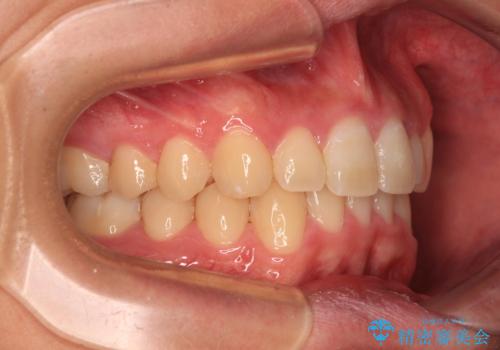

- 上下前歯のデコボコと深い咬み合わせを気にして来院された患者様です。

下顎前歯が一本欠損しており、下顎の歯列が小さいため、ディープバイトになりやすい状態でした。

傾斜しいている大臼歯を立ち上げながら、下顎歯列を上顎に対して前方位となるように工夫し、デコボコを解消した上でディープバイトも改善することができました。